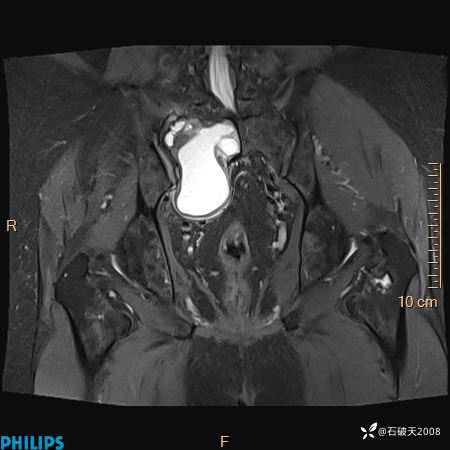

2023年3月份MRI影像

T2压脂冠状位